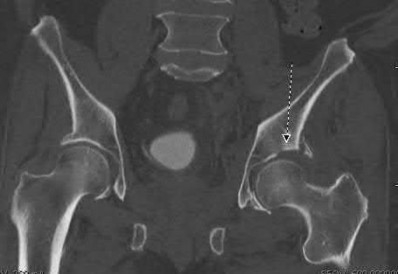

A 27 year-old patient sustains a fracture-dislocation of the acetabulum. Pelvic radiographs (Figures A and B) are taken at initial presentation and a CT scan (Figures C and D) is performed after reduction of the hip in the emergency room. What is the importance of the finding highlighted in the CT scan cuts?

The CT images shown in Figures C and D display significant marginal impaction of the joint surface.

Marginal impaction is common in posterior wall fractures and fracture-dislocations. Critical review of CT imaging of posterior wall fractures can help with preoperative planning for identifying impaction of the articular surface of the acetabulum. Restoration of the sphericity of the acetabulum to match that of the femoral head is important for successful outcome following ORIF of posterior wall fractures. A common surgical technique to accomplish joint surface restoration includes freeing the impacted articular segments, bone grafting of the void created to support the articular segments, and buttress plating of the posterior wall fracture fragments.

Figures A and B are radiographs of the posterior wall fracture and hip dislocation. They do not show the large amount of marginal impaction of the acetabular surface. Figure C (coronal reconstruction) and Figure D (sagittal reconstruction) point out a large a amount of marginal impaction of the acetabular. Note the disruption of the joint surface on the intact portion of the acetabulum.